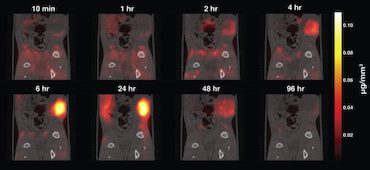

Magnetic particle imaging for early cancer detection

Magnetic particle imaging is a new, up-and-coming, safe and highly sensitive tracer imaging technique that works by detecting superparamagnetic iron oxide nanoparticles with high image contrast (that is, no background tissue signal). The technique, which does not use any ionizing radiation, can be used to image anywhere inside the body, which means that it could […]